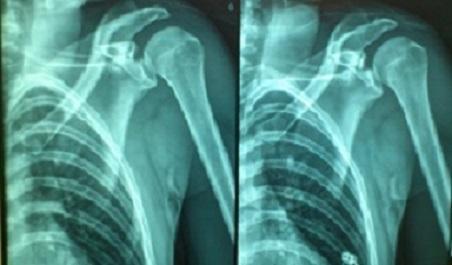

Pan Afr Med J. 2015 Mar 19;20:268. doi: 10.11604/pamj.2015.20.268.6433. eCollection 2015.